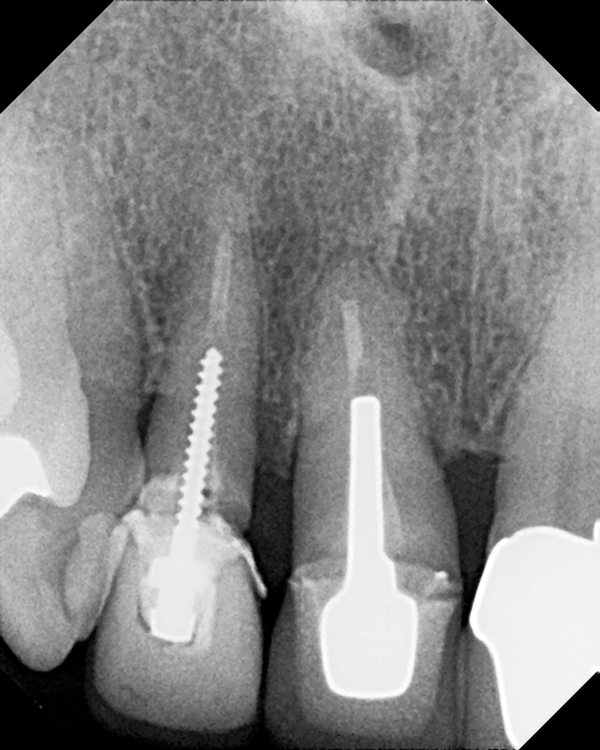

(3.) Radiograph of a loose screw-style metal post.

Figure 3

(4.) Radiograph of a root fracture that occurred at the end of a parallel metal post.

Figure 4